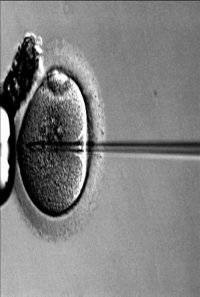

La quimioterapia y radioterapia puede destruir las células germinales en ovarios y testículos, provocando así infertilidad en las personas que han superado un cáncer, según ha alertado el especialista en Ginecología y Medicina de la Reproducción en la Unidad de Reproducción Asistida del Hospital Vithas Nuestra Señora de América, Juan Ordás.